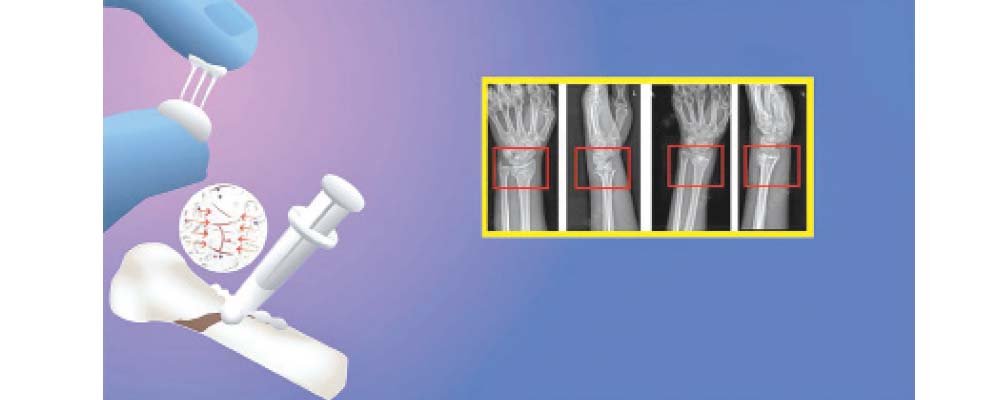

भाँच्चिएको हड्डी क्षणभरमै जोडिने

चीनका वैज्ञानिकले विश्वमा पहिलो पटक हड्डी जोड्ने बोन ग्लु तयार पारेका छन् । जसले भाँच्चिएको हड्डीलाई २/३ मिनेटमै जोड्दछ । बोन ग्लु सामुद्रिक सिपीबाट प्रेरित छ । यो छ महिनामा शरीरमै घुल्ने बायोडिग्रेडेबल पदार्थ हो । चीनको वेन्झोउमा डाक्टर लिन जियानफेङ्गको टोलीले डेढ सयभन्दा धेरै बिरामीमा यसको परीक्षण गरी यो सुरक्षित र प्रभावकारी रहेको साबित गरेको छ ।

डाक्टर लिनले समुद्रमा लहर तथा ज्वारभाटामा समेत सिपी नामक जीव नबगेर अडिग रहन सक्ने तथ्यको आधारमा रगतले भरिएको वातावरणमा हड्डीलाई पनि जोड्न सकिन्छ कि भन्ने विचार गरे । सोही विचारका आधारमा उनले उक्त बोन ग्लु बनाए । उक्त ग्लुले दुई सय केजीभन्दा धेरै तौल भएको वस्तुलाई समेत टाँस्ने क्षमता राख्दछ । सर्जरी गरी उक्त ग्लु लगाउनाले भाँच्चिएका हड्डी २–३ मिनेटमै जोडिन्छन् ।

पुरानो विधिमा भाँच्चिएका हड्डी जोड्नलाई धातु प्रत्यारोपण गर्नु पर्दछ । जसलाई हटाउनका लागि अर्को सर्जरी आवश्यक हुन्छ तर बोन ग्लु छ महिनामा भाँच्चिएको हड्डी पूर्ण रूपमा जोडिएर ठिक भएसँगै आफैँ घुल्दछ र अर्को सर्जरी आवश्यक पर्दैन ।

वैज्ञानिकले यो ग्लु बनाउने क्रममा ५० भन्दा धेरै सूत्र र सयौँ परीक्षण गरेका थिए । यो पदार्थ जैविक रूपमा सुरक्षित छ र भाँच्चिएको हड्डीलाई जोडिएर निको हुन मद्दत गर्दछ ।

विश्वमा हरेक वर्ष विविध कारणले करोडौँ मानिसको हड्डी भाँचिने गर्छ । परम्परागत विधिबाट धातु प्रत्यारोपण गरी हड्डी जोड्दा सङ्क्रमणको खतरा पनि रहन्छ । यस्तो अवस्थामा बोन ग्लु कैयौँ समस्याको समाधान हुने छ ।